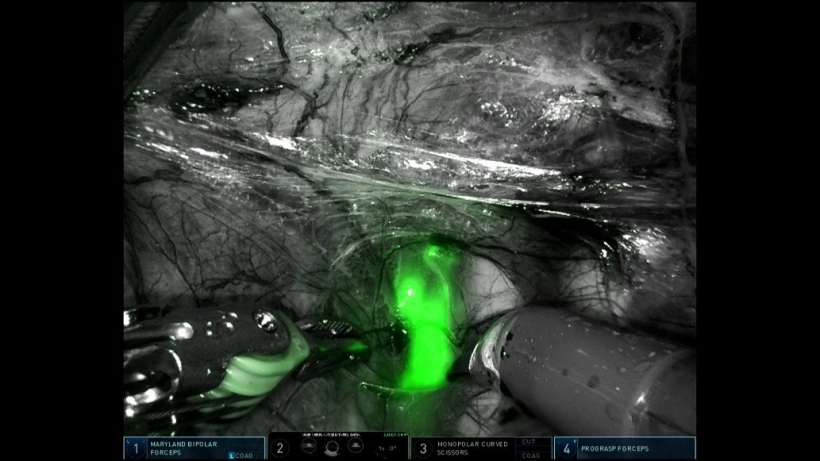

Sinds kort gebruiken we bij andere typen kanker een nieuwe techniek voor de schildwachtklierprocedure . Hierbij wordt een fluorescent groene marker ingespoten tijdens de operatie (indocyanine groen). Deze groene marker is niet zichtbaar met het blote oog maar wel met een speciale camera.

Aan het begin van de operatie zal de gynaecoloog de groene marker inspuiten rondom de tumor. Deze groene marker wordt ingespoten in aanvulling op de radioactieve en blauwe marker. Tijdens de operatie sporen we de schildwachtklieren eerst op met de groene marker, met behulp van een speciale camera. Daarna vergelijken we de klieren die groen oplichten met de huidige techniek: we kijken of deze klieren ook radioactief en blauw zijn. Vervolgens verwijderen we de gevonden schildwachtklieren. Daarna beoordelen we het operatiegebied nogmaals op de aanwezigheid van radioactieve of blauwe klieren die eventueel zijn gemist met de groene marker.

Hieronder staat een voorbeeld van hoe een schildwachtklier groen oplicht met gebruik van de speciale camera.